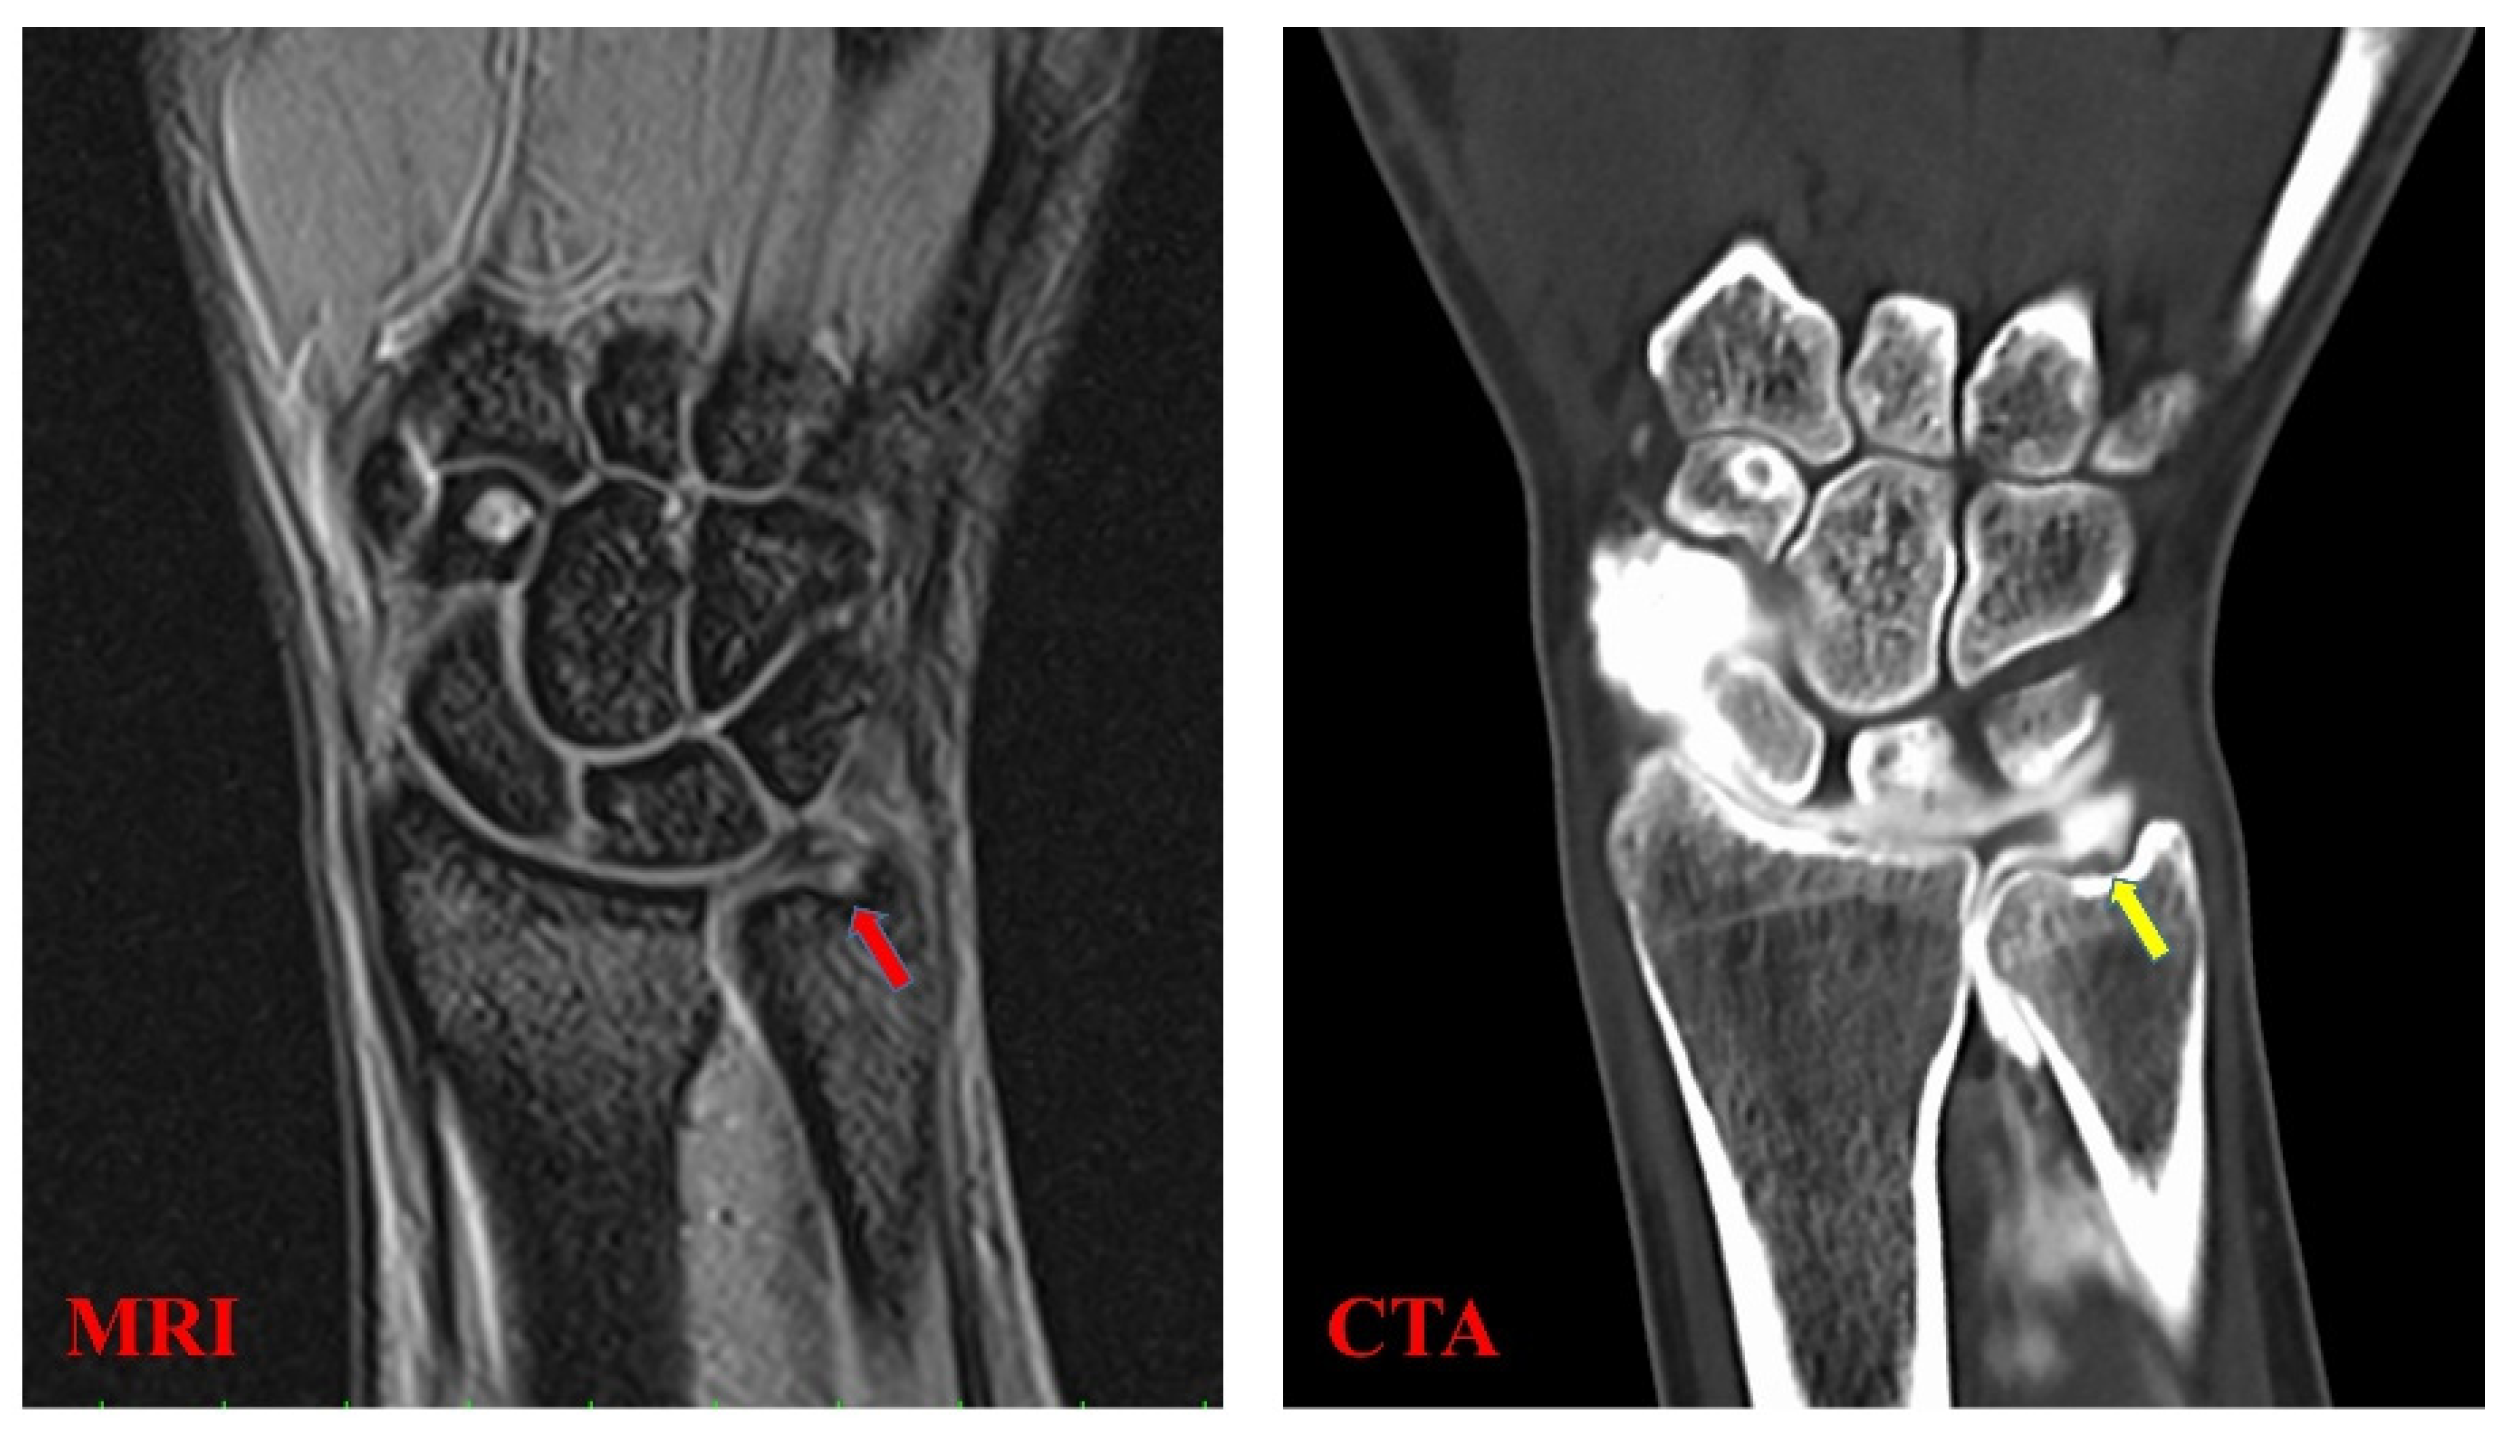

The TFCC is a complex soft tissue structure which cannot be evaluated by simple X-ray or computed tomography [4]. Therefore, magnetic resonance imaging (MRI) and computed tomographic arthrography (CTA) are used for the diagnosis of TFCC injuries (Figure 2); however, it is not easy to diagnose damage within the TFCC due to its small, thin, and complex structure [4]. According to a meta-analysis that analyzed the utility of different imaging modalities for TFCC injury, the sensitivities were 0.76 and 0.89 for MRI and CTA, respectively, while the specificities were 0.82 and 0.89, respectively [4]. Ultrasonography (US) has recently been used as a low-cost, minimally invasive option for the diagnosis of musculoskeletal disorders. Wu et al. presented a standard US scanning protocol for TFCC in 2019 by observing the volar and dorsal sides of the wrist joint [5]. Furthermore, US can depict components of the TFCC and elaborate existing lesions of the articular disc, meniscus homologue, and juxta-articular ligaments. However, the protocol in 2019 was described only for static image analysis [5], and dynamic analysis has not yet been performed. Previous MRI analyses have shown that the TFCC’s morphology is different between healthy volunteers and patients with Palmer type 1B TFCC injuries (radial and ulnar deviation, respectively) [6]. Therefore, we proposed that US-based observation of this morphological change would lead to the diagnosis of TFCC injury.

Figure 2.

TFCC injury (Palmer type 1B) delineation via magnetic resonance imaging (MRI) and computed tomographic arthrography (CTA). MRI T2* imaging shows a high-intensity line on the disc of the TFCC (red arrow). Moreover, CTA pooling of the contrast medium at the TFCC attachment site of the ulnar head is visible (yellow arrow).